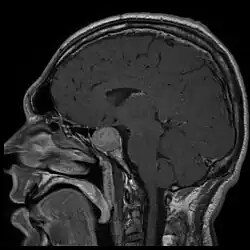

A acromegalia é geralmente causada pela produção excessiva de hormona do crescimento pela hipófise.[1] Em mais de 95% dos casos esta produção excessiva é o resultado de um tumor benigno, como um adenoma de hipófise.[1] A doença não é hereditária.[1] Em casos raros, a acromegalia pode ser causada por um tumor noutra parte do corpo.[1] O diagnóstico consiste em medir os níveis de hormona do crescimento após a ingestão de uma solução de glicose, ou em medir a concentração no sangue do fator de crescimento semelhante à insulina tipo 1.[1] Após o diagnóstico são realizados exames imagiológicos à hipófise para determinar a presença ou não de um adenoma.[1] Quando a produção excessiva de hormona do crescimento ocorre durante a infância, o resultado é uma doença denominada gigantismo, e não acromegalia.[1]